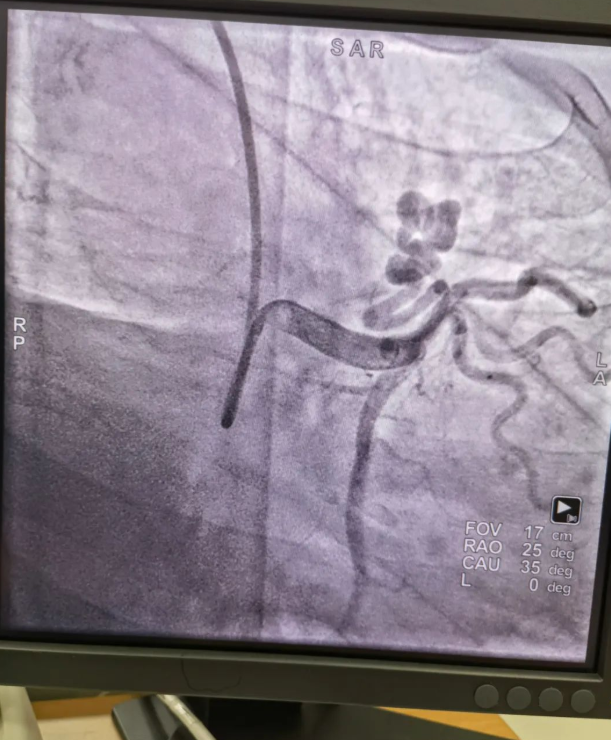

不久前,來自新疆的患者石先生去年至今反復(fù)胸悶、氣短、胸痛,就診于新疆某院,懷疑“冠心病”,住院行冠狀動脈造影術(shù),石先生造影提示“冠狀動脈肺動脈瘺”,而他并非“冠心病”,所以給予的“冠心病”治療,效果不佳。出院后仍反復(fù)出現(xiàn)胸痛、胸悶、氣短等癥狀,經(jīng)親友介紹了解到西安國際醫(yī)學(xué)中心醫(yī)院心臟病醫(yī)院心臟內(nèi)科二病區(qū)曾廣偉主任,多年來潛心研究心臟病介入治療,成功主刀救治了許許多多高危復(fù)雜病例,尤其是在先心病及結(jié)構(gòu)性心臟病封堵,以及冠心病、心律失常射頻消融及起搏治療等方面積累了豐富的診療經(jīng)驗(yàn)。

此病例罕見,在曾廣偉從醫(yī)18年生涯里曾碰到有2個印象深刻的病例,患者分別是53歲和66歲,當(dāng)時建議患者入院進(jìn)行動脈瘺的封堵術(shù),但患者和家屬考慮到這個手術(shù)案例極少,風(fēng)險也高,均未接受手術(shù)治療建議,只是能采取藥物保守治療,出院后隨訪得知患者癥狀緩解效果不佳,后來在隨訪中也與53歲患者失去了聯(lián)系,而66歲患者因冠狀動脈肺動脈瘺出現(xiàn)反復(fù)心衰,在當(dāng)?shù)蒯t(yī)院藥物治療,短短2年時間,患者因?yàn)閯用}瘺未及時手術(shù)失去了生命。所以此次患者石先生到訪,曾廣偉主任在詳細(xì)掌握病例資料基礎(chǔ)上,果斷建議進(jìn)行動脈瘺的封堵術(shù)治療,為了提高手術(shù)成功率和精準(zhǔn)度,曾廣偉主任搜集相關(guān)診療資料,反復(fù)推演論證,經(jīng)過相當(dāng)充足的準(zhǔn)備工作,于5月18日成功進(jìn)行了封堵手術(shù),完全堵上了瘺口。

患者術(shù)后第2天,已經(jīng)沒有明顯的胸悶、氣短、胸痛等癥狀,目前身體狀態(tài)良好。本次手術(shù)曾廣偉主任及其團(tuán)隊(duì),采取從右手臂一根血管進(jìn)入,并在2小時之內(nèi)完美封堵,創(chuàng)口小,痛苦小。手術(shù)雖然難度大、風(fēng)險高,相關(guān)案例也少,但是曾廣偉主任主刀即在巔峰,這樣一臺完美的手術(shù)靠的不是運(yùn)氣,是豐富的臨床手術(shù)經(jīng)驗(yàn),扎實(shí)的專業(yè)知識儲備,以及對醫(yī)療事業(yè)的孜孜追求。

冠狀動脈瘺是指冠狀動脈與心腔、冠狀靜脈、肺動脈等的異常連接,是一種少見的先天性心臟病,發(fā)病率為1.3%。而冠狀動脈肺動脈瘺是冠狀動脈與肺動脈之間產(chǎn)生的一種血管性瘺口,導(dǎo)致冠狀動脈里的血液流入肺動脈里,使冠狀動脈里血液流量減少,出現(xiàn)心肌供血不足,冠狀動脈肺動脈瘺會使患者出現(xiàn)胸部疼痛、胸悶、呼吸困難、頭暈、乏力等一系列癥狀,隨著疾病不斷進(jìn)展,可引發(fā)心功能的障礙和心肌缺血,肺動脈會逐漸形成肺動脈高壓,還可能導(dǎo)致動脈瘤的破裂,甚至威脅病人的生命安全,所以早期發(fā)現(xiàn)和治療冠狀動脈肺動脈瘺,對病人的預(yù)后改善具有重要的意義。